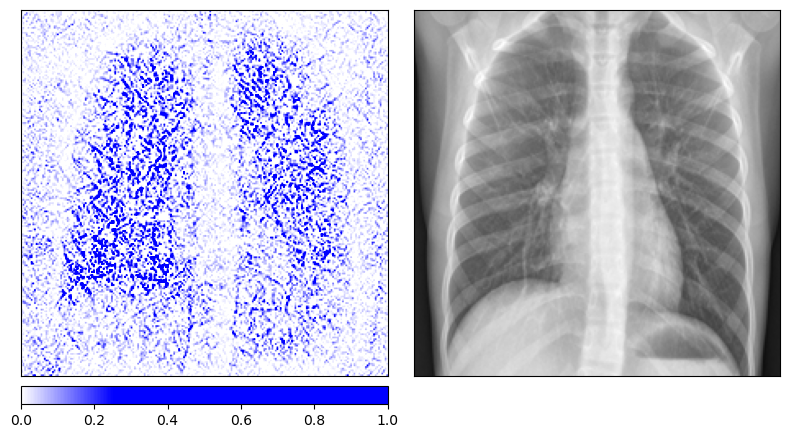

We retrain the same ResNet-50 architecture on the pneumonia dataset with randomly permuted training labels for 200 epochs. As expected, the model’s balanced accuracy drops to 0.52, essentially random chance. The Integrated Gradients maps for the permuted-label model look qualitatively different from those of the properly trained model. The attributions for healthy and diseased patients become indistinguishable, with both showing a similar scattered pattern that outlines anatomical structures without any class-specific focus.

Integrated Gradients on truly healthy patients (permuted-label model)

|

Both methods pass the data randomization test. The attribution maps change substantially when the model is trained on meaningless labels, confirming that they reflect the model’s learned decision function rather than low-level image properties. This is an important validation step that is often overlooked when deploying explainability tools in practice.